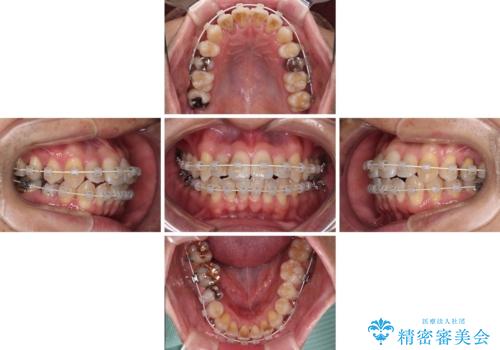

- 矯正装置

- 審美装置

- 治療期間

- 2年2ヶ月

舌の突出癖の影響か、下顎前歯がなかなか整わず、治療期間は予定よりも長期間となりました。

舌突出癖改善のトレーニングの重要性を認識することとなりました。